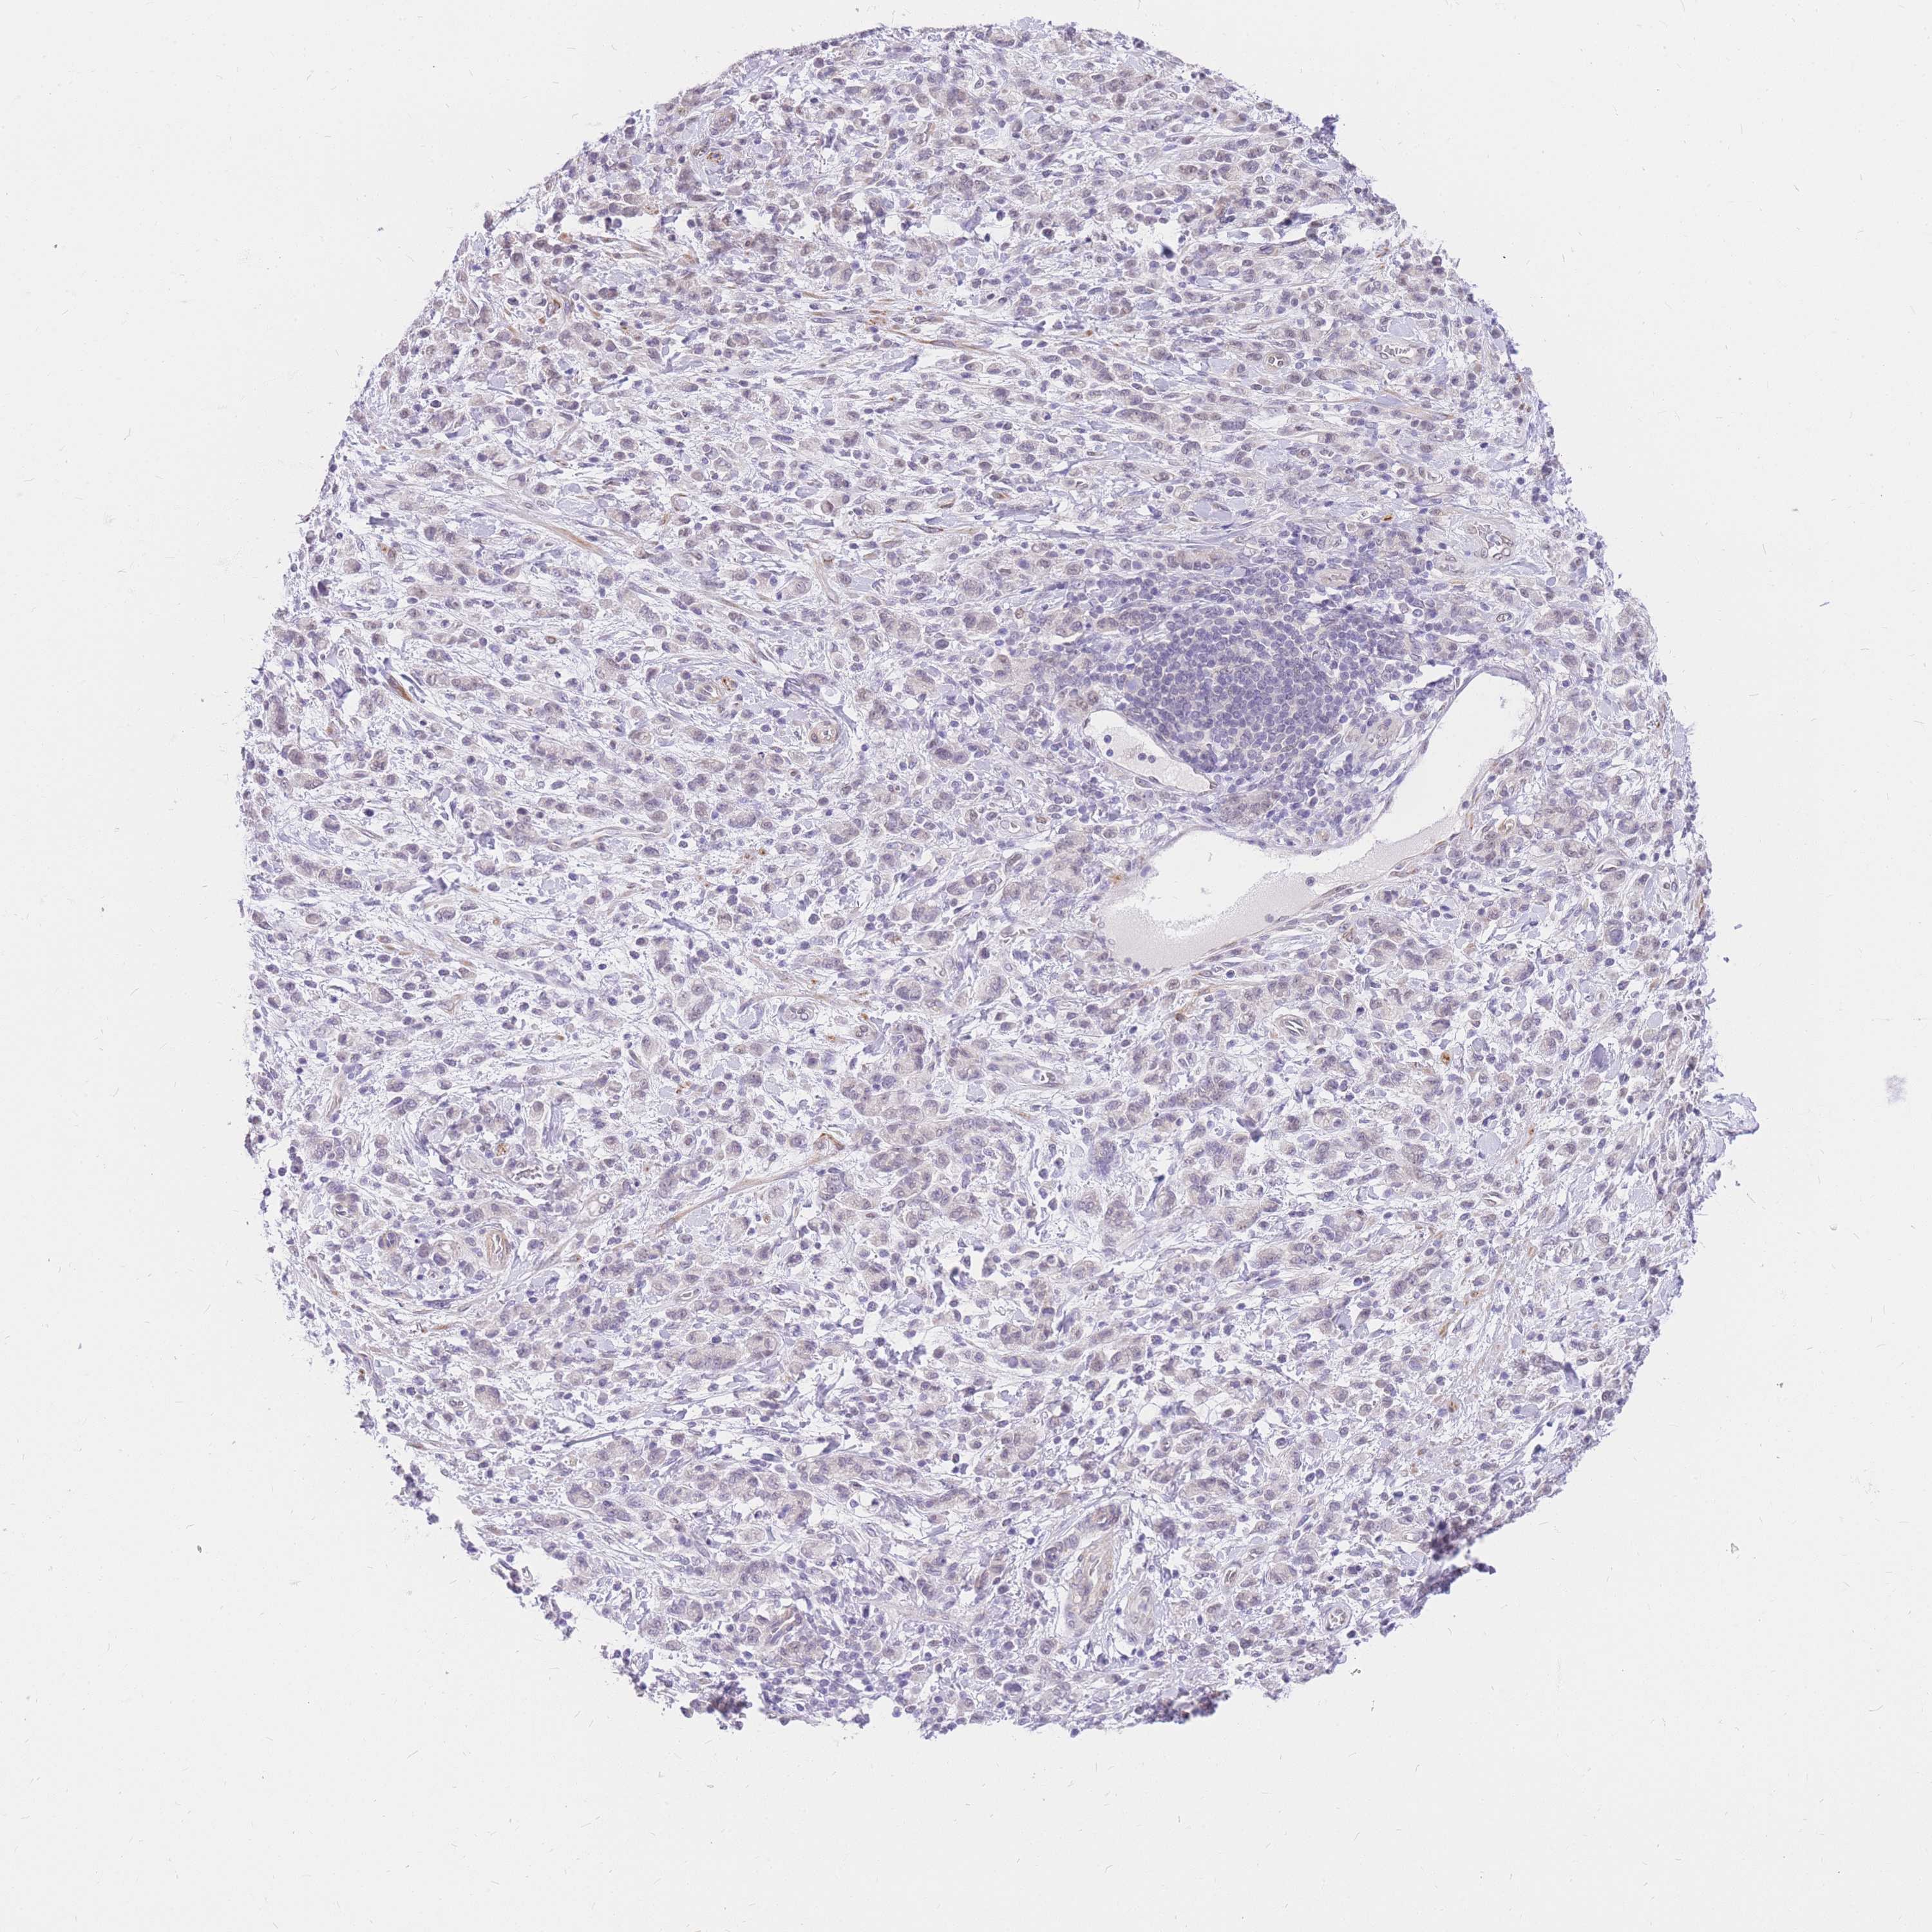

STOMACH CANCER - Protein expressioni

A mouse-over function shows sample information and annotation data. Click on an image to view it in a full screen mode. Samples can be filtered based on level of antibody staining by selecting one or several of the following categories: high, medium, low and not detected. The assay and annotation is described here.

Note that samples used for immunohistochemistry by the Human Protein Atlas do not correspond to samples in the TCGA dataset.

Antibody stainingi

Antibody staining in the annotated cell types in the current human tissue is reported as not detected, low, medium, or high, based on conventional immunohistochemistry profiling in selected tissues. This score is based on the combination of the staining intensity and fraction of stained cells.

Each image is clickable and will lead to virtual microscopy that enables deeper exploration of all samples and also displays staining intensity scores, fraction scores and subcellular localization as well as patient and tissue information for each sample.

Antibody HPA027242

Antibody HPA027328

Staining

High

Medium

Low

Not detected

Intensity

Strong

Moderate

Weak

Negative

Quantity

>75%

75%-25%

<25%

None

Location

Nuclear

Cytoplasmic/membranous

Cytoplasmic/membranous,nuclear

Adenocarcinoma, NOS